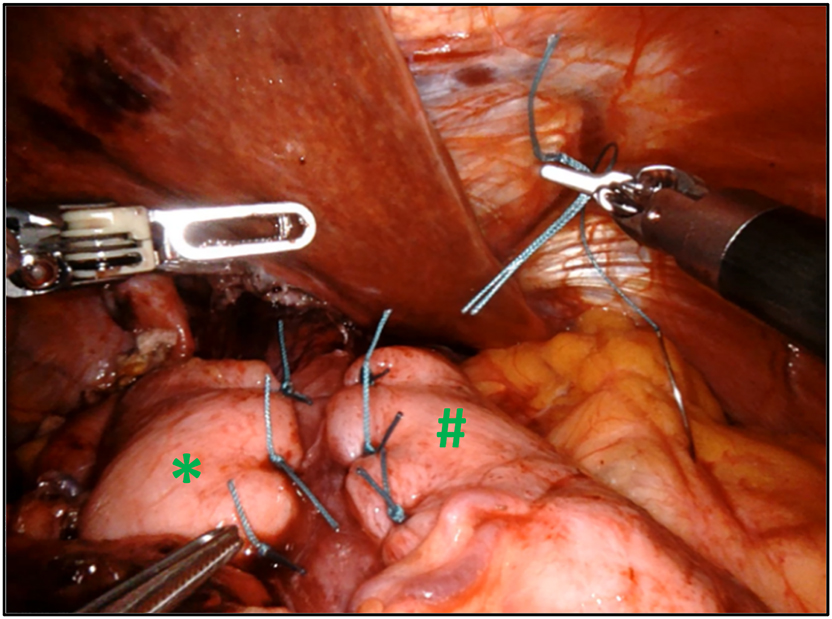

Voluminous hiatal hernia with a large hiatal defect (#). After introduction of the trocars into the abdominal space, the liver retractor (*) is placed in order to lift the left lateral lobe of the liver and give access to the esophageal hiatus. The procedure can then start with opening of the pars flaccida of the hepatogastric ligament (✩) to access the right diaphragmatic crus.